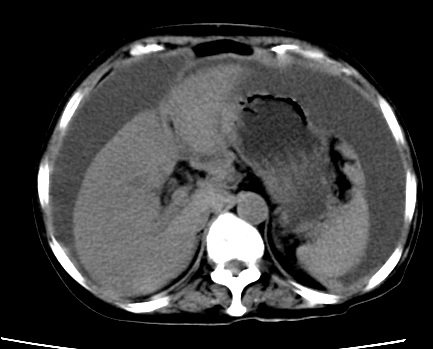

标题: CT23975:女61岁,腹部不适,明显消瘦

既往5年前卵巢癌行子宫及附件切除,右乳癌术后一年,考虑腹膜转移?

大量腹水,考虑腹膜转移。肝脏低密度灶。1囊肿,2转移。

1)结合病史,考虑腹膜及网膜转移瘤。2)肝脏多发性低密度灶,不排除转移瘤。3)大量腹水。

考虑卵巢癌行子宫术后复发,并肝、腹腔 、大网膜转移可能性大。

大量腹水。